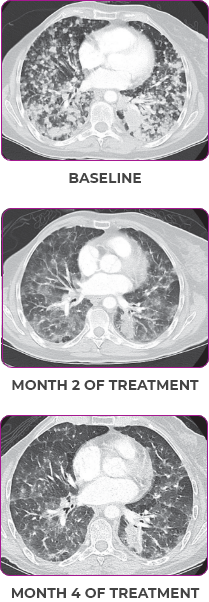

MRIa imagery of the brain. Green circles indicate baseline brain metastases.1

SCAN 2: BRAIN

aMRI, magnetic resonance imaging.

MRIa imagery of the brain. Green voxels indicate decreased burden of metastatic disease; further quantified by accompanying measurement in green.1

SCAN 3: BRAIN

- Partial response to treatment that was confirmed at 2 months (34% tumor reduction)

- Grade 1 cough and Grade 2 fatigue

- Patient remains on VITRAKVI after more than 4 months of treatment